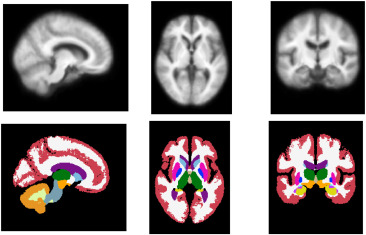

图4. 通过对训练数据中前100名受试者进行平均来构建模板。上图:通过平均获得的强度模板。下图:与平均强度模板对应的标签图。通过平均构建的模板明显不如AtlasMorph模板清晰。